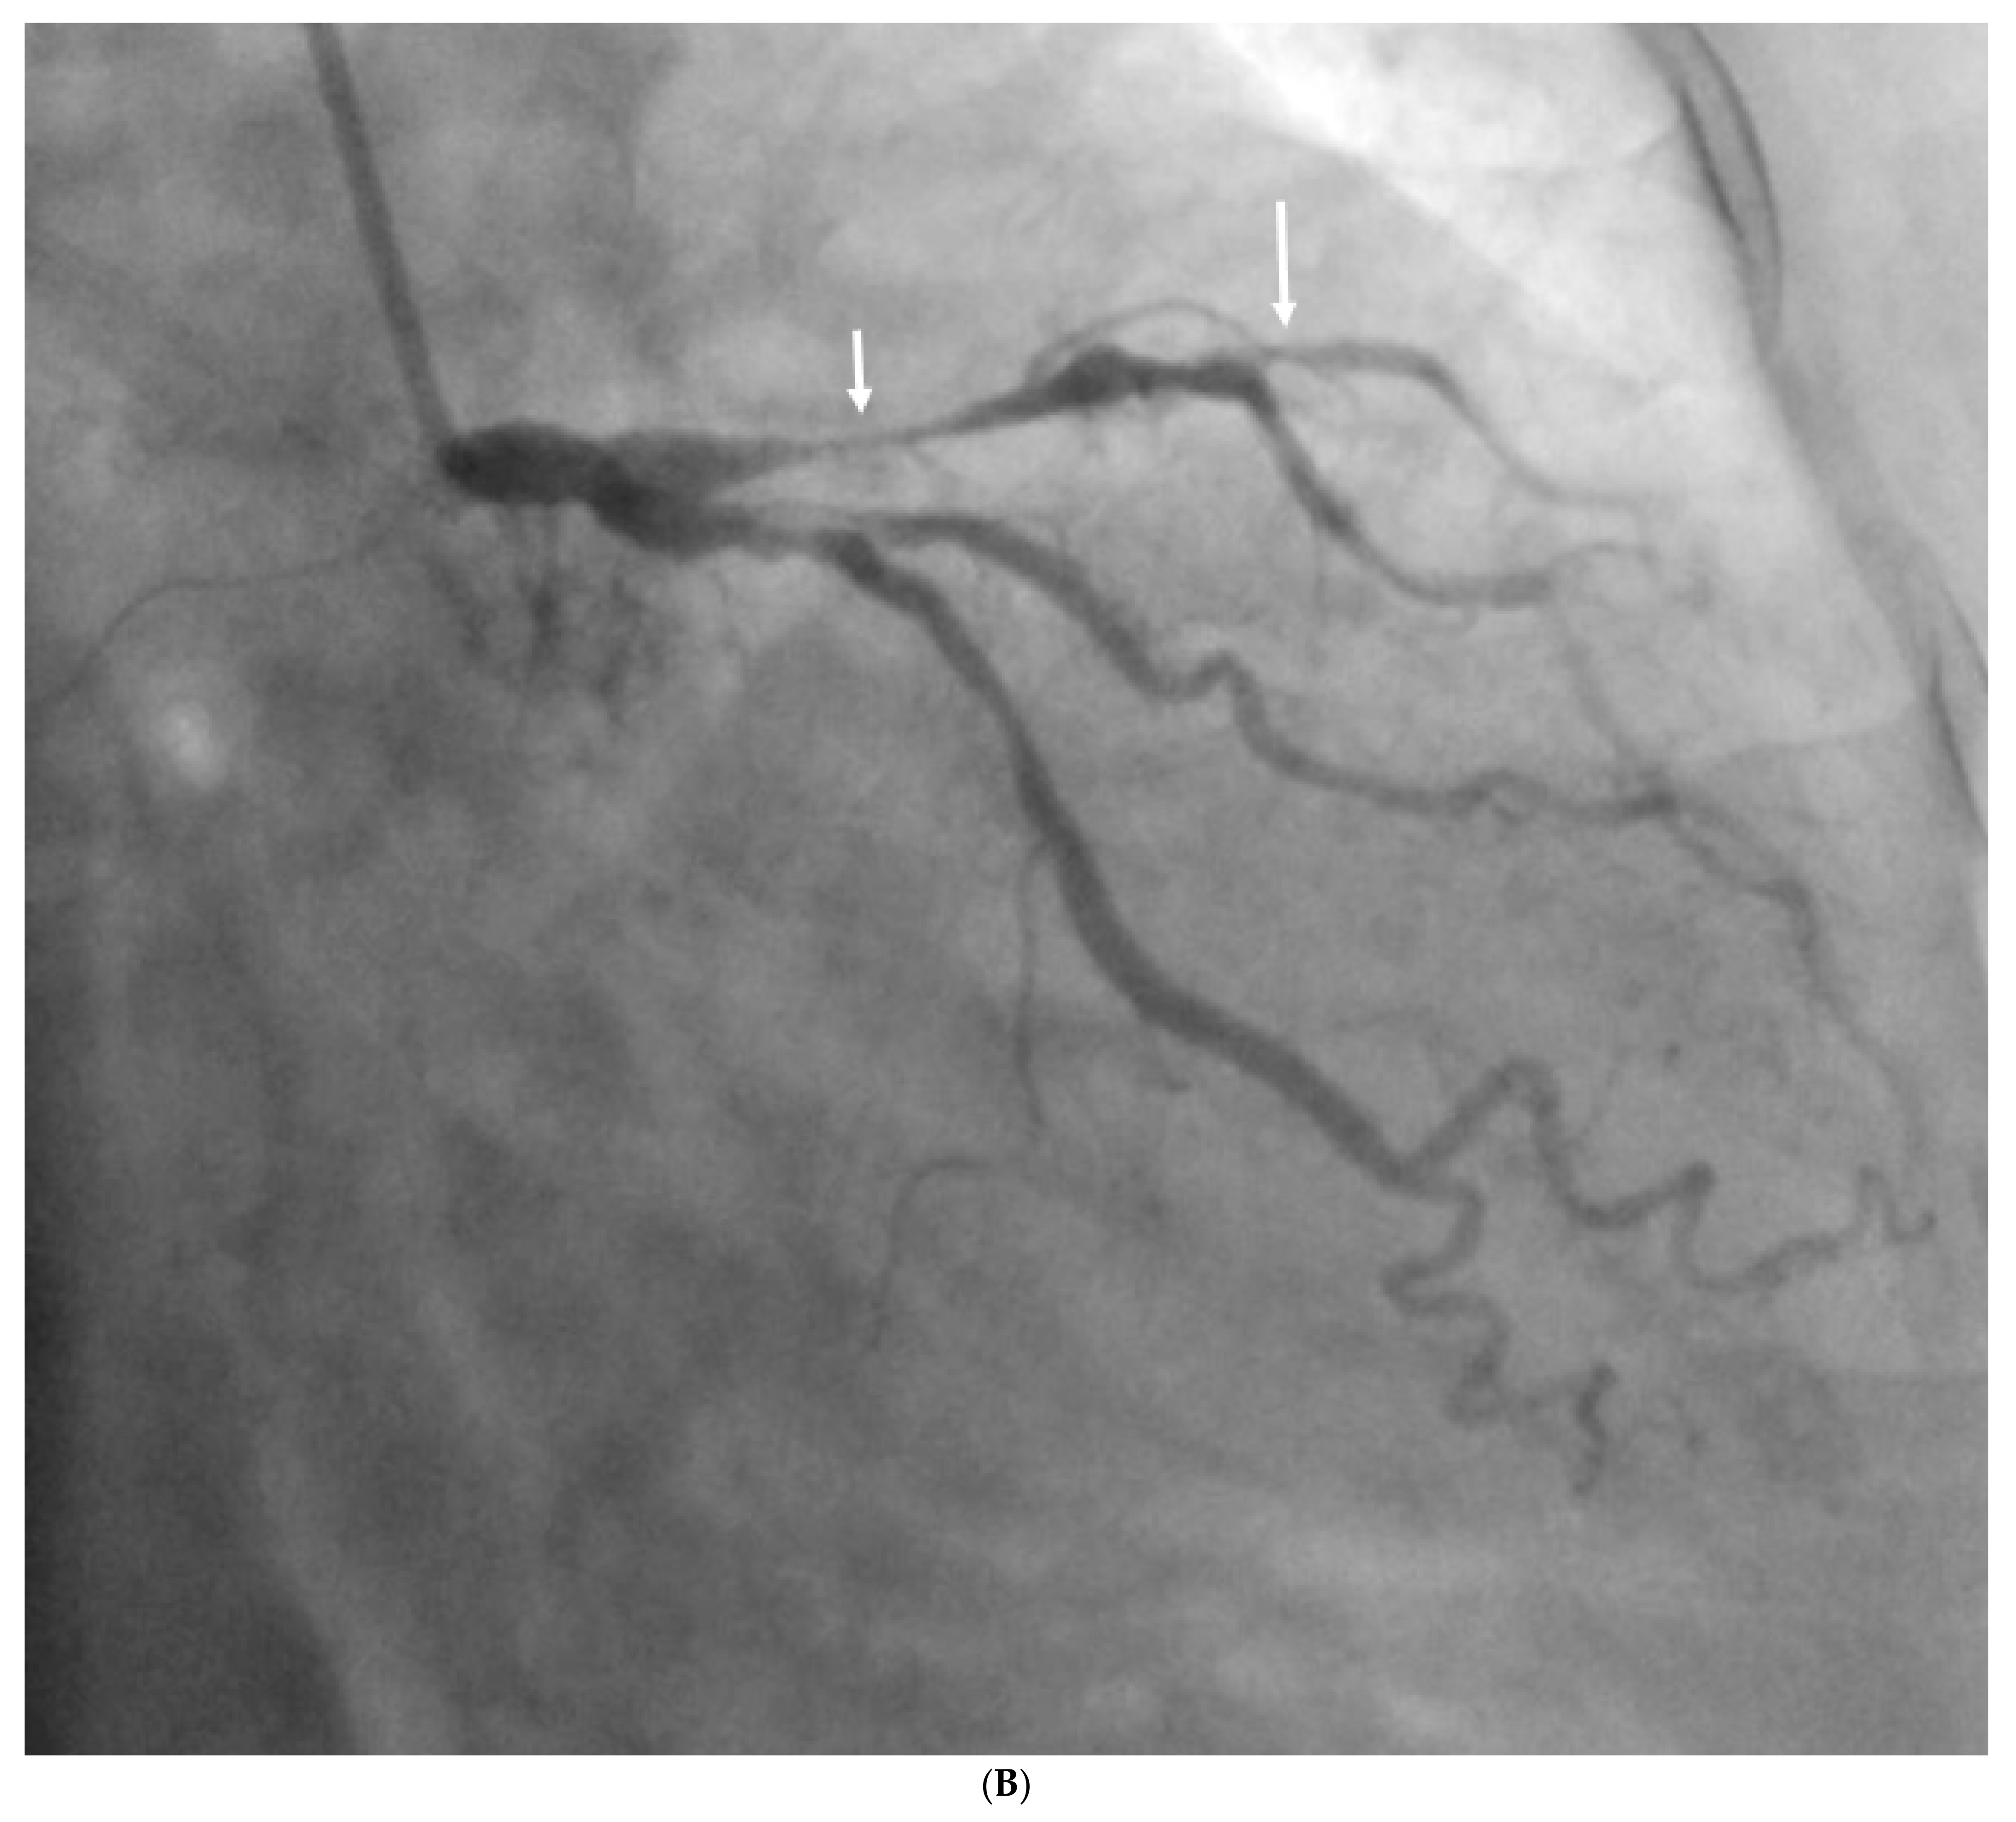

- Sun, Z.; Ng, C.K. Artificial intelligence (enhanced super-resolution generative adversarial network) for calcium deblooming in coronary computed tomography angiography: A feasibility study. Diagnostics 2022, 12, 991. [Google Scholar] [CrossRef]

- Sun, Z.; Ng, C.K. Finetuned super-resolution generative adversarial network (artificial intelligence) model for calcium deblooming in coronary computed tomography angiography. J. Pers. Med. 2022, 12, 1354. [Google Scholar] [CrossRef]